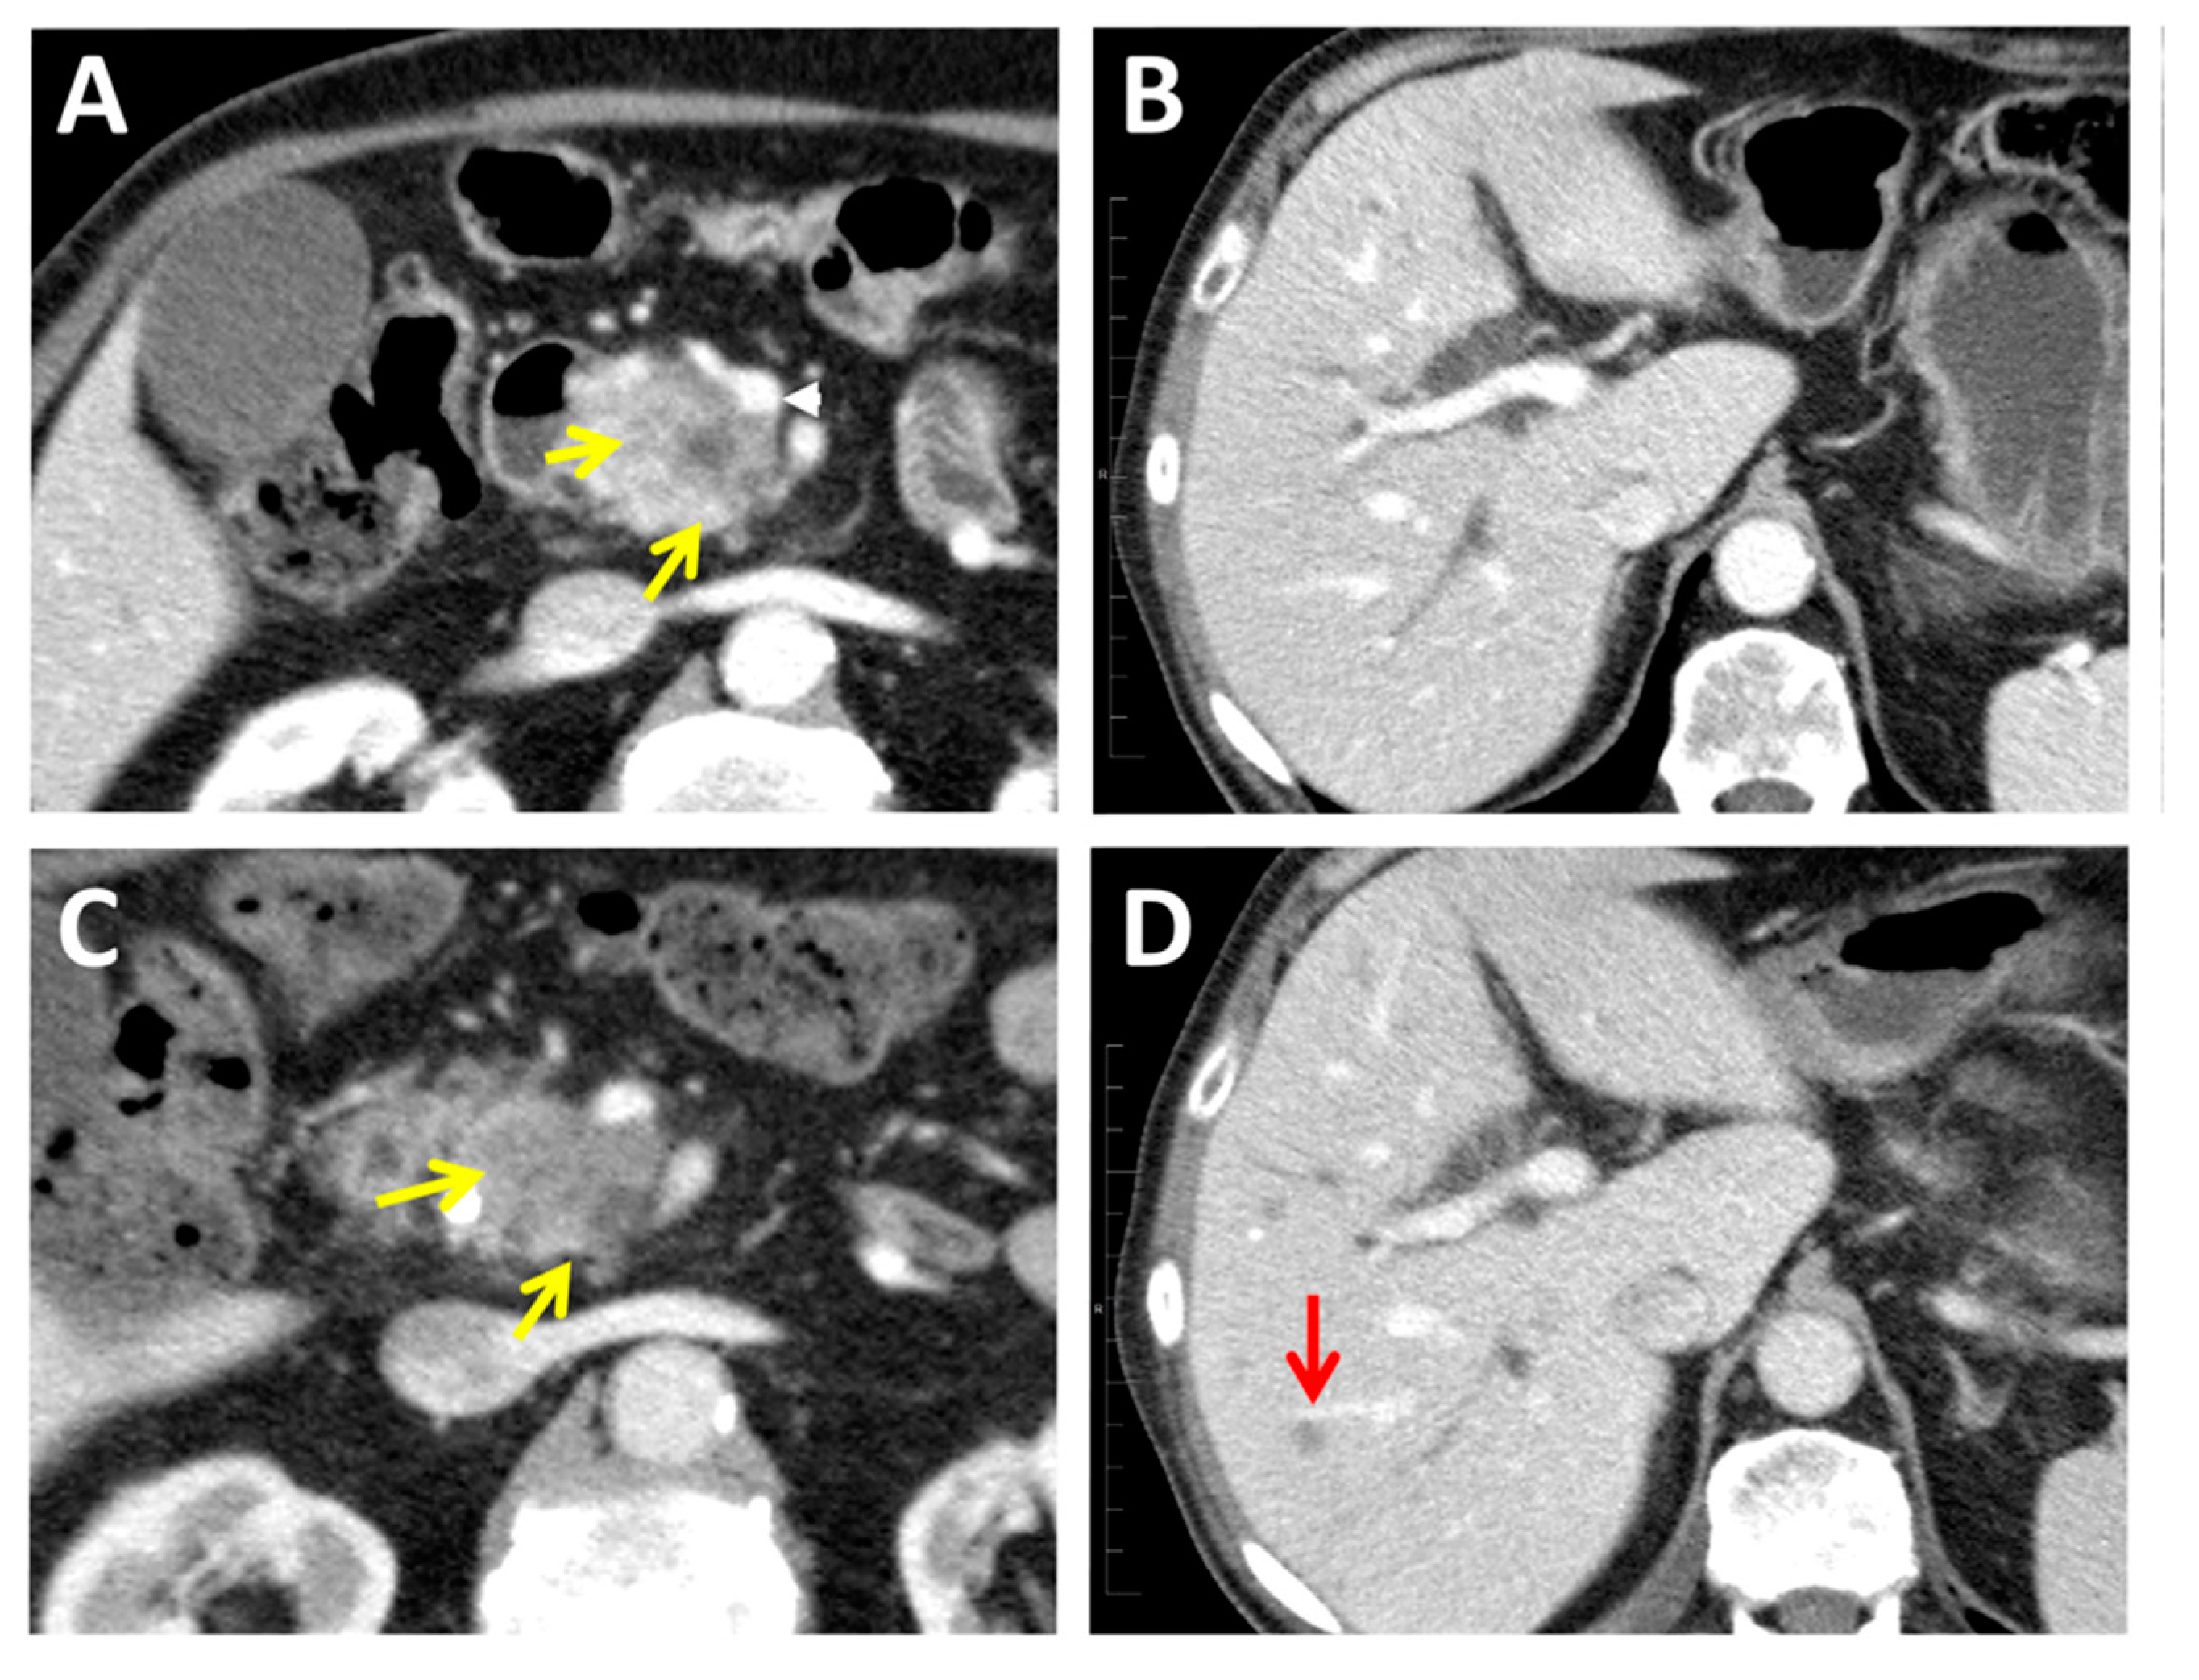

- Ishigami, K.; Yoshimitsu, K.; Irie, H.; Tajima, T.; Asayama, Y.; Nishie, A.; Hirakawa, M.; Ushijima, Y.; Okamoto, D.; Nagata, S.; et al. Diagnostic value of the delayed phase image for iso-attenuating pancreatic carcinomas in the pancreatic parenchymal phase on multidetector computed tomography. Eur. J. Radiol. 2009, 69, 139–146. [Google Scholar] [CrossRef]

- Ahn, S.S.; Kim, M.J.; Choi, J.Y.; Hong, H.S.; Chung, Y.E.; Lim, J.S. Indicative findings of pancreatic cancer in prediagnostic CT. Euro. Radiol. 2009, 19, 2448–2455. [Google Scholar] [CrossRef]